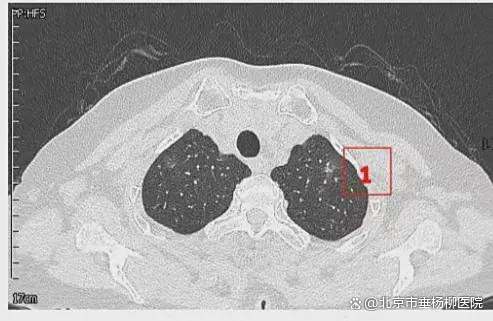

患者女性,71岁,因“发现左肺多发结节2周”入院。胸部CT提示左肺多发磨玻璃结节,较大者位于左肺上叶,呈类圆形,边界清晰,最大直径约9mm。该CT表现高度提示恶性可能。鉴于患者结节数量较多,为减少术中肺组织损伤,术前于CT引导下行经皮肺结节定位术,继而实施胸腔镜下左肺楔形切除术。术中共切除肺部结节6枚。术后病理示:左肺上叶较大结节(4号)为微浸润腺癌,其余5枚结节均为原位癌。患者术后恢复良好,于术后第1天拔除胸腔引流管,第4天顺利出院。

影像资料